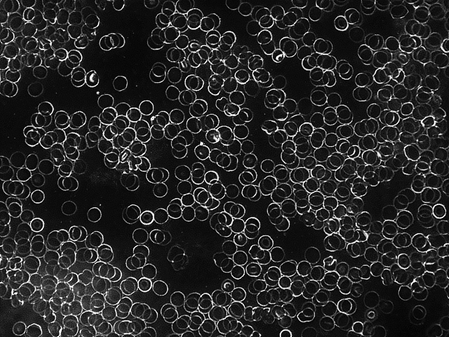

Telefonat mit GEOenergetic Handy-Transmitter

Auch nach einem 10-minütigem Telefonat mit dem GEOenergetic-Handytransmitter bewahren die roten Blutkörperchen  ihre ursprüngliche Mobilität bzw. fangen an, sich voneinander zu lösen.

Der Einsatz des GEOenergetic Handy-Transmitter wirkt sich positiv auf die elektrische Ladung aus.  Es kann somit eine normale Entwicklung ablaufen.

Besonderheit

In den Versuchen, bei denen bereits vor dem ersten Handy-Telefonat leichte Verklumpungen in Form von sog. Geldrollen vorlagen, wirkte sich der GEOenergetic-Handy-Transmitter positiv aus. Nach dem Telefonat mit dem Handy-Transmitter waren Auflösungen dieser ursprünglichen Verklumpungen nachweisbar. Dies lässt sich durch die Veränderung des elektrischen Potentials erklären.